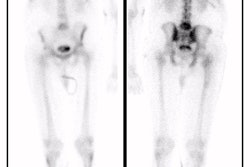

Acute renal failure is characterized by relative preservation of renal blood flow and extraction of tubular agents with a rising renogram curve (Retained cortical activity at 20 minutes (RCA) will be almost 100%). Extraction of glomerular agents in acute renal failure is low. The kidneys are usually of normal size.

In chronic renal failure there is severely and proportionately reduced renal blood flow and tracer extraction of both tubular and glomerular agents. The kidneys are often small in size. The renogram curve is typically flat with a low count plateau. In end-stage renal failure the kidneys are only faintly discernible from blood pool activity.